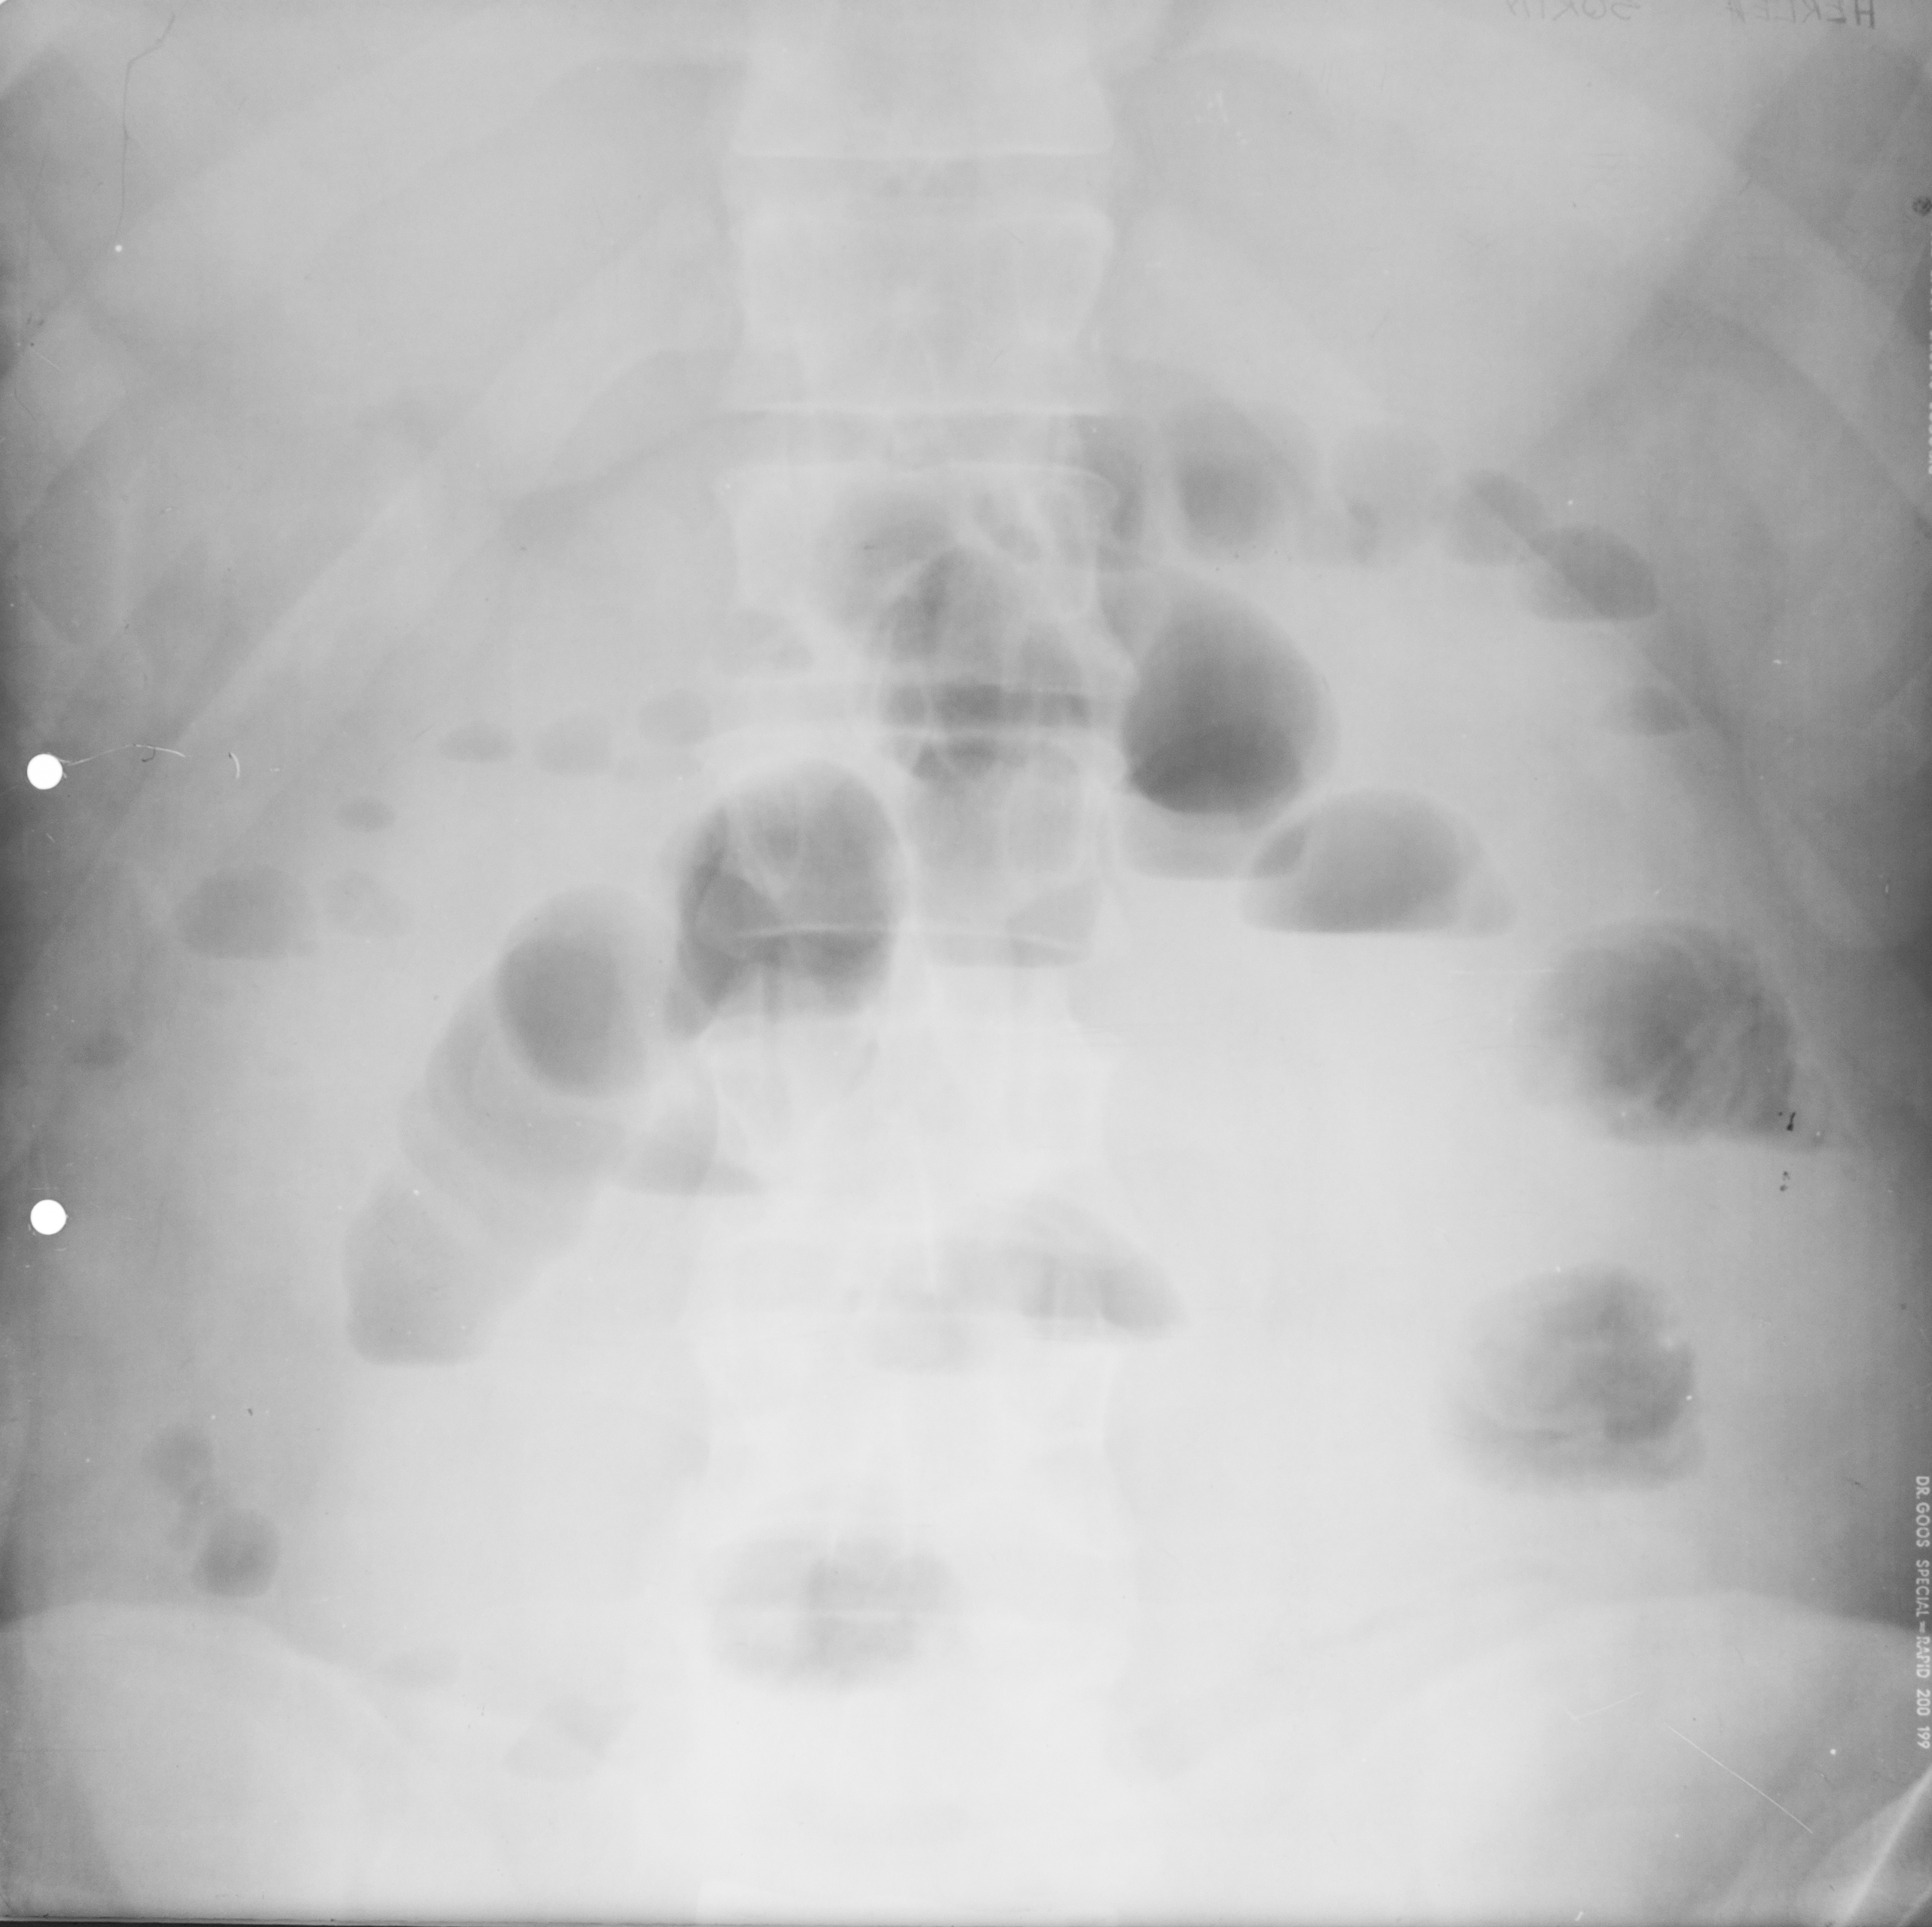

: IRIGOGRAFIE

Aspect radiologic al irigoscopiei unde recunoastem cec ascendent, flexura hepatica , transvers care este ptozat si e singura modificare care nu este neaparat patologica, flexura splenica, colon desccendent, sigmoid si rect. Absolut normal pentru persoana relativ in varsta

DEFECT DE UMPLERE (IRIGOSCOPIE/IRIGOGRAFIE)

Este rotund, bine net liniar delimitat, probabil ceva polip

DIVERTICULI (IRIGOGRAFIE)

Multiple imagini de aditie la nivelul cadrului colic

STENOZA MALIGNA = ADENOCARCINOM DE COLON

Tot irigografie cu zona de stenoza la nivelul colonului transvers, vedem coloana vertebrala si colon descendent, cu contur neregulat la extremitati, cu aspect de cotor de mar

Tot irigografie.

Zona de stenoza la nivelul colonului descendent si retrodilatatie cu aspect de pantalon de golf, proces infiltrativ la nivelul colonului. Mai putin frecvent decat adenocarcinomul

PROCES NEOPLAZIC CU STENOZĂ

Colon descendent, sigma, zona de stenoza fara mucoasa la nivelul acestei zone, proces neoplazic.

NEOPLASM

Aspect de cotor de mar cu stenoza, contur neregulat, retrodilatatii,lipsa lizereului de siguranță,deci lipsa mucoasei la acest nivel. Neoplasm

OCLUZIE LA NIVELUL INTESTINULUI SUBȚIRE

Radiografie abdominala pe gol, in etajul mijlociu, multiple imagini hidroaerice, cu ax transversal hidroaeric, cu ax transversal mai mare decat axul craniocaudal. Nivele hidroaerice de tip intestin subtire

OCLUZIE(situată mai jos) SAU ILEUS DINAMIC

Nivele hidroaerice de tip intestine gros, cu ax mare vertical si nivele hidroaerice de tip intestin subtire, posibil ocluzia este undeva mai jos sau sa fie Ileos dinamic

Imagine hidroaerica tipica de intestine gros, ax mare vertical, ax mare vertical mai mare decat ax orizontal, se vad haustrele deci clar se poate recunoaste colonul